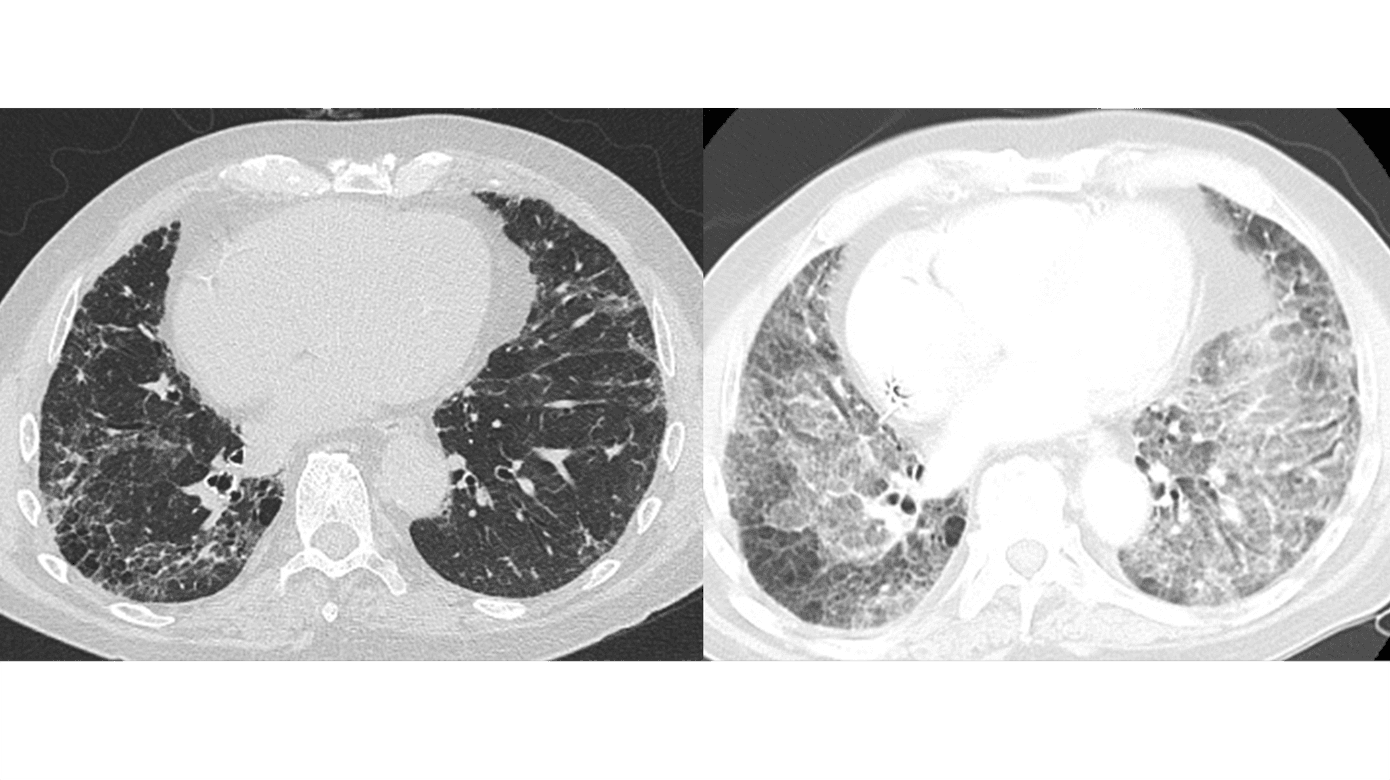

HRCT er nødvendig for at kunne stille diagnosen AE-IPF. Ved AE-IPF ses nyopstået bilateral matglastegning (hyppigst) og/eller konsolidering (sjældnere) oven i et underliggende kendt eller nydiagnosticeret usual interstitial pneumonia (UIP)-mønster (Figur 2) [10]. Disse radiologiske fund indgår i de diagnostiske kriterier for AE-IPF (Tabel 2) [2].

AE-IPF har kliniske og histopatologiske ligheder med acute respiratory distress syndrome, idet begge kendetegnes af akut respiratorisk forværring, bilaterale matglasforandringer og konsoliderende infiltrater på CT af thorax samt et histopatologisk diffuse alveolar damage-mønster [9].